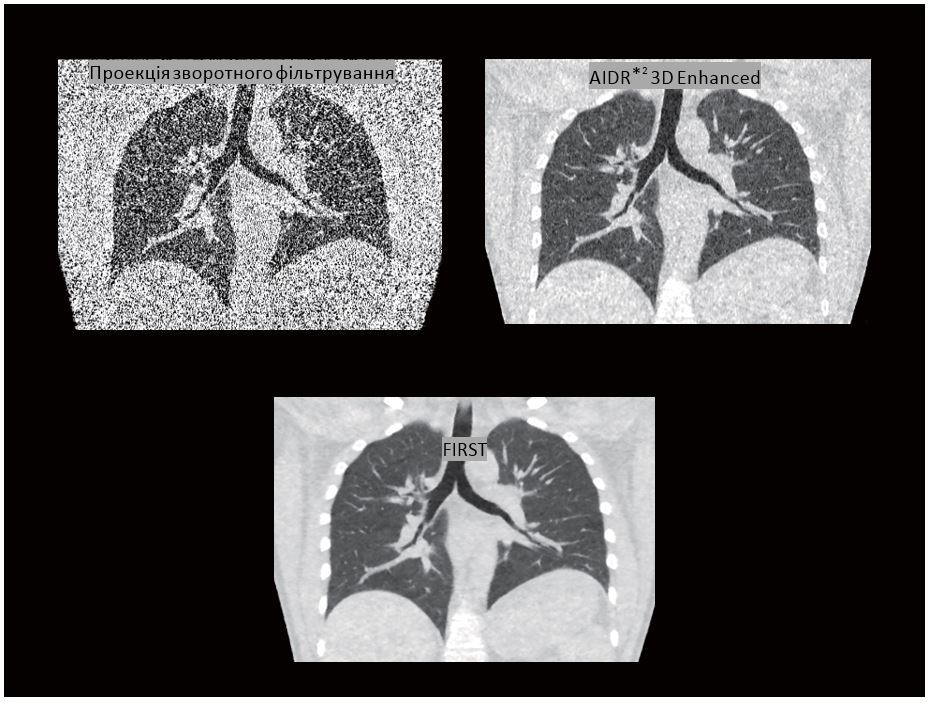

На зображенні візуалізується невеликий ателектаз у нижньому відділі легені. Отримана пацієнтом доза при цьому дослідженні становила 0,08 мЗв.

Алгоритм ітеративної реконструкції на основі прогнозованої моделі (FIRST*1) є справжнім алгоритмом MBIR (Model-Based Iterative Reconstruction), це означає, що крок прямої проекції виконується для кожної ітерації. FIRST забезпечує покращену просторову роздільну здатність із високою контрастністю та зменшення дози до 82,4% у порівнянні з проекцією зворотного фільтрування.

FIRST здатний надавати зображення легень із покращеною просторовою роздільною здатністю з рівнем дозового навантаження, як під час проведення рентгенографії  грудної  клітки.